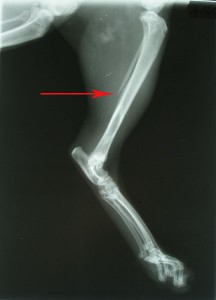

Po operaci obou kostí